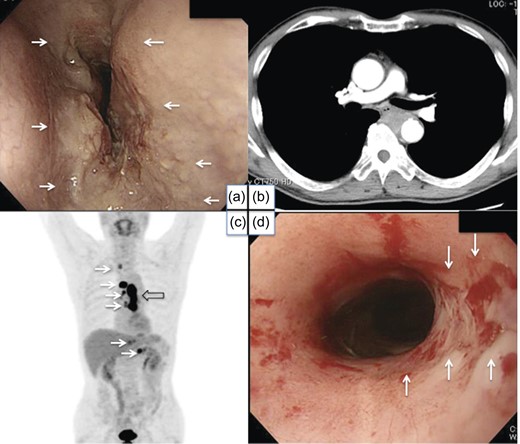

A 64-year-old male consulted one of our hospitals due to progressive dysphagia in August 2012. An endoscopic examination revealed middle thoracic ESCC (Fig. 1). Computed tomography (CT) scans showed possible invasion of the aorta and multiple lymph node metastases (T4bN3M1 stage4) (Fig. 1). The length of the tumor was ∼10 cm on CT scans. The patient received definitive chemoradiotherapy [two courses of cisplatin and 5-fluorouracil (FP) plus 50.4 Gy] followed by one course of FP chemotherapy, and incomplete response/stable disease was achieved. Although an endoscopic biopsy specimen was positive for cancer (Fig. 1), post-treatment CT showed no invasion of the aorta. Fluorine-18-fluorodeoxyglucose positron emission tomography (FDG-PET) also suggested that the size of the tumor was diminished. The patient underwent colonoscopy to prepare for colonic interposition because the radiation field included the upper part of the stomach. Preoperative colonoscopy revealed a 1.0-cm submucosal tumor at the splenic flexure, and biopsy results indicated possible metastasis from primary ESCC (Fig. 2). The submucosal lesion was positive for cytokeratin 5/6 (CK5/6), CK14 and p63, and negative for CK20 and Caudal type homeobox 2 (CDX2) (Fig. 2). Colonic metastasis was not detected by FDG-PET before or after chemoradiotherapy. No other obvious hematogenic metastases were noted after chemoradiotherapy.

Pretreatment endoscopic examination, CT scan, FDG-PET and post-treatment endoscopic examination. A tumor was found in the middle thoracic esophagus (a). CT scans revealed possible invasion of the aorta (b) and multiple lymph node metastases. FDG-PET also suggested the spread of tumors (open arrow) and multiple lymph node metastases (white arrows) (c). Post-treatment endoscopy showed a marked reduction in the size of the tumor, while residual carcinoma cells were detected in a biopsy specimen (white arrows) (d).